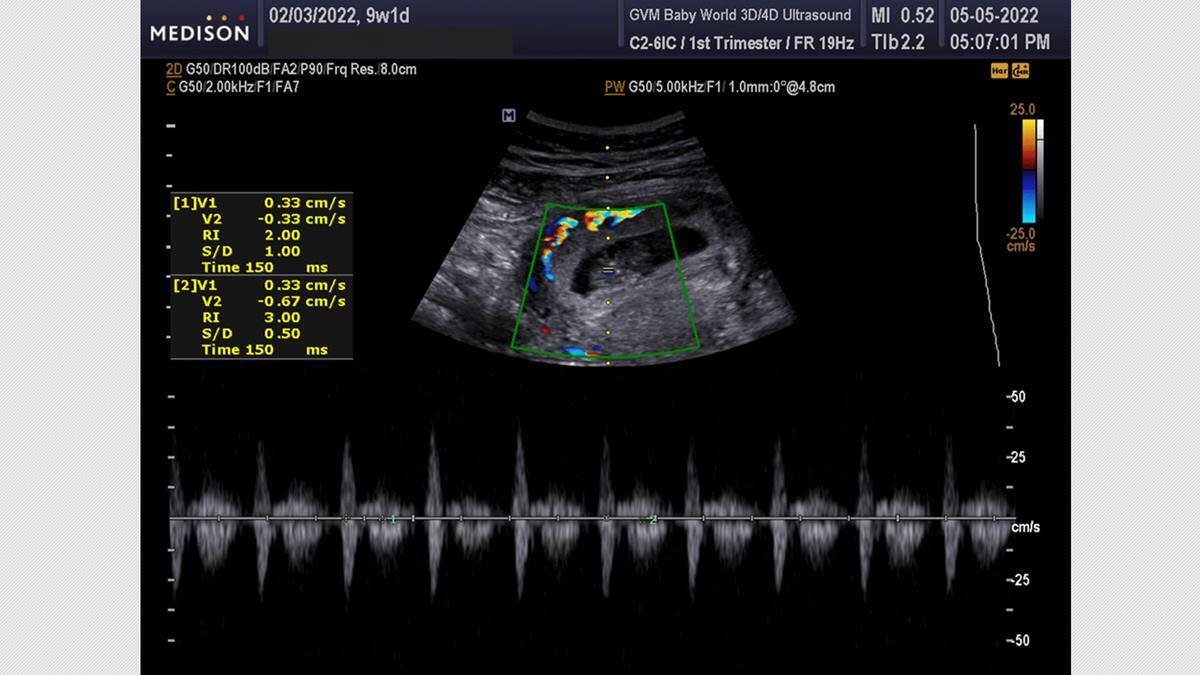

Una ecografía 5D puede detectar el latido fetal a las cuatro semanas de la fecundación, y con mayor claridad a partir de las seis semanas y media o siete semanas. Foto: Baby World Ultrasound.